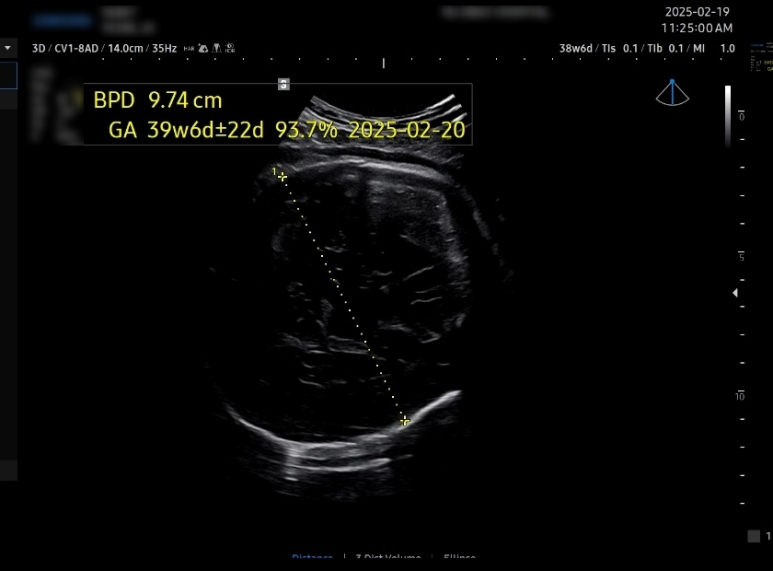

38주에 머리둘레 9.74cm 몸무게 3.5kg

38주 6일차